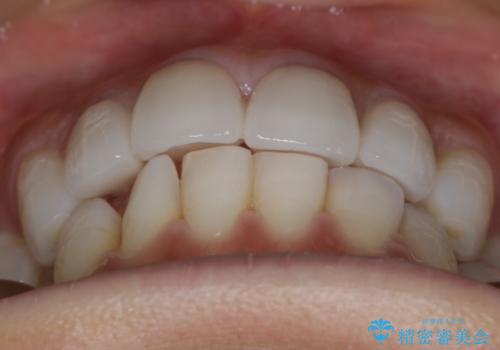

- 嚙み合わせのズレを主訴にご来院されました。

前歯・奥歯ともにセラミッククラウンで治療されている歯があったため、その歯にあまり影響が出ない範囲内で全体の噛み合わせが良くなるような動きを組み込んで治療を進めることとなりました。